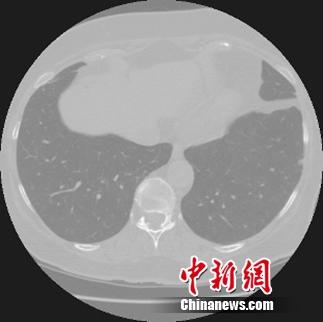

天池是全球规模最大的众智平台,汇聚了6万多名AI算法科学家。医疗大数据平台零氪科技为大赛提供经脱敏处理并由专家标注的高清胸部CT扫描影像数据。选手需要通过原始CT影像图片训练模型算法得到结节特征,最终实现对影像图片结节区域的智能化判断。

结节是影像学上的一个描述性名词,只有在发现结节之后才能进一步确认是良性还是恶性。因此,对于肺癌的筛查来说,准确发现结节是诊断的第一步。

一位经过严格训练,有着多年临床经验的医生,诊断一个病例平均需要查看200张以上的CT扫描图片,诊断时间在20分钟以上。而计算机结节检测系统通过学习大量有经验医师标注的样本,能在短时间内快速提升诊断能力,辅助基层医疗机构的医生减少误诊。